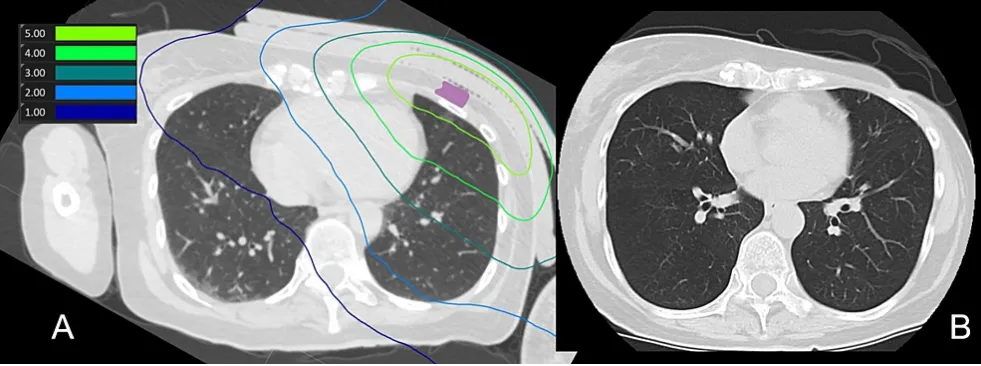

該患者在BNCT治療前有6年以上的左側(cè)乳腺癌化療史,隨后進(jìn)行了乳房切除,并對(duì)左側(cè)胸壁區(qū)域進(jìn)行了30次放射治療,總劑量為54Gy。首次放療三年后左胸復(fù)發(fā),通過手術(shù)、放療和化療進(jìn)行了治療。再次復(fù)發(fā)時(shí),進(jìn)行了BNCT治療。最低處方劑量為23.6Gy-Eq,同側(cè)肺的平均劑量為2.7Gy-Eq。在BNCT治療后第1、3、7、30、60和90天進(jìn)行了CT掃描,結(jié)果均未發(fā)現(xiàn)放射性肺炎跡象。圖2為肺部劑量分布以及治療90天后的CT掃描結(jié)果。

圖2

(A) BNCT(肺)劑量分布圖。紫色表示腫瘤總體積

(B) 治療后90天CT掃描,未見放射性肺炎征象,且腫瘤總體積縮小